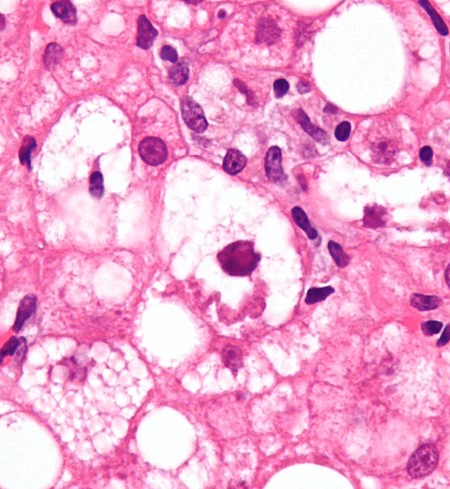

endometrial cancer